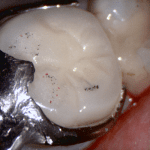

This case was scanned by two different scanners. Once by the Medit i500 and another time with the Aoralscan. Both the meshes are included so you can compare the two. It was scanned to deliver a case that retrofits a partial denture